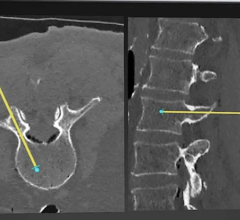

- XRware Tomography Reconstruction to generate object model from its projections using artifact-reduced approaches using whatever trajectories and acquisition constraints (partial scan, low dose acquisitions). Features include analytical approaches, exact reconstruction algorithm, approximated reconstruction algorithms (FDK/FBP, BFP), acquisition strategies (circular, non-circular, helix, complex trajectories), extended view, partial scan, iterative approaches (deterministic and stochastic approaches), automatic Hounsfield unit calibration, automatic geometry parameters adjustment.

- XRware 3-D Image Processing to experience volume processing for a more accurate analysis. Features include noise reduction, contrast enhancement, sharpening, ring artifact reducer, beam hardening reduction, metal artifact reduction, scatter reduction